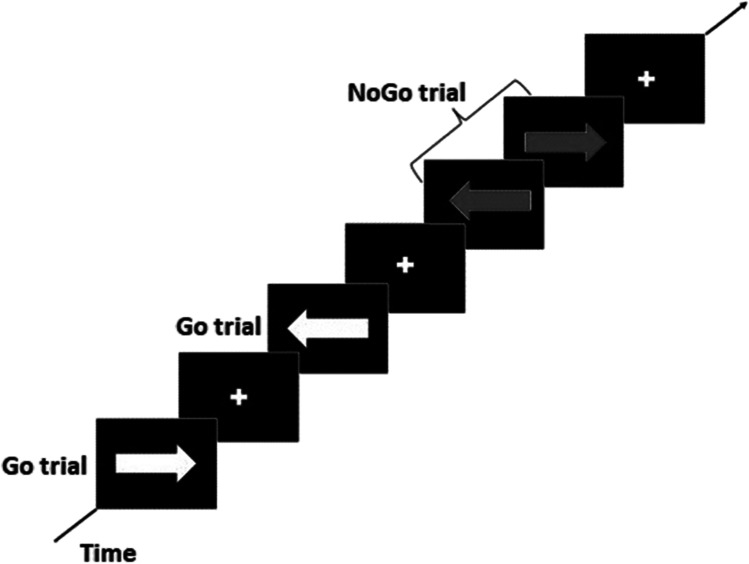

Go/NoGo task

The Go/NoGo is a computerized task used to study sustained attention and inhibitory control as hallmarks of executive functioning, which is generally altered in substance-abuse disorders (Verbruggen & Logan, ref. 2008). This task measures the capacity to inhibit a pre-potent response (i.e., dominant or automatic motor response). It consists in left- or right- pointing arrows appearing briefly on the screen, participants must select the corresponding on the keyboard as fast as possible (Go condition). Randomly on 20% of trials, the arrow color changes to blue, this represents the NoGo condition in which the motor response must be inhibited Fig. 1.

The parameters of the task were set as follows:

- Maximal reaction time: 1.0 s

- Intertrial interval: 0.25 s

- Initial signal delay: 0.250 s

- Numbers of experiment blocks: 2

- Delay between blocks: 30 s, with feedback on the performance of each block.

The random list for signal presentation was organized with 10 Go stimuli and 2 NoGo stimuli (1/6 of the trials were NoGo trials). The task included 1 practice block, which contains 24 trials with 20 Go and 4 NoGo stimuli, and 2 experimental blocks in which design was repeated 20 times. At the end of the task, the subject’s performance parameters were recorded, as the numbers of Go and No-Go responses for each condition: correct, incorrect on a NoGo, incorrect on a Go, and missed.

Results were analysed using the framework of Signal Detection theory (Macmillan & Creelman, ref. 2005), which attributes responses to a combination of sensitivity (as detecting a signal, i.e., Go) and specificity (i.e., NoGo). Here, accuracy is represented by the Hit rate (success rate), i.e., the proportion of correct responses on Go trials (conversely known as omission errors) and was used as an index of attentional performance (Li et al., ref. 2006; Saunders et al., ref. 2008). The proportion of incorrect responses on NoGo trials (i.e., commission error) was used as an index of inhibitory control (Li et al., ref. 2006; Macmillan & Creelman, ref. 2005).